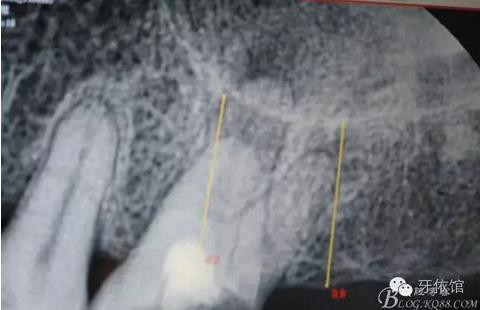

患者女,45歲,右上6于多年前牙髓失活后充填,未作冠,術前不久,進食時不幸劈裂。檢查發(fā)現(xiàn):右上6充填物脫落,近遠中向縱劈,x光見根管內(nèi)無充填物。同時有右上7、右下7缺失。計劃:右上6,7,右下7種植修復。右上6為即可種植,同時做內(nèi)提。

X光片

術后x光片,右上6直接上愈合基臺,但未完全就位,右下7手術過程略

這是術后1月的片子,重新就位愈合基臺